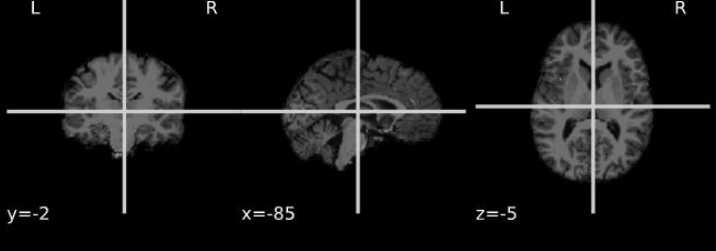

The PPMI dataset contains MRI images of patients in DICOM (Digital Imaging and Communications in Medicine) format files [50], which represents a two-dimensional image of a single angle of the person; therefore, the first step of the pre-processing was the reconstruction in a three-dimensional format, or in NIfTI (Neuroimaging Informatics Technology Initiative) [74], a format notoriously used in the medical field. Fig 4(a) shows the original DICOM format of an MRI belonging to PPMI visualized by using the tool “MicroDicom” [36], while Fig. 5(b) shows the three-dimensional NIfTI format if the same image produced by the “MRIcroGL”[70] tool.

Figure 6: Example of templates.